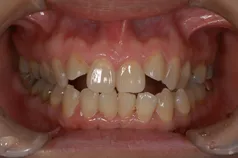

[症例]

矯正治療を行っています。

治療前は上下の歯が反対になっている所もあり、上の歯の真ん中から2本目の歯は矮小歯と言って、平均より小さな歯のため上唇が引っ込んで見えます。

インビザラインでマウスピース矯正後、オフィスホワイトニングを行い、矮小歯はラミネートベニアで修復しました。

綺麗な歯並びになるとともに、上顎の歯列のアーチが広がって、上唇がやや前方に出ることで自然な口元になりました。

- 治療期間: 1年6ヶ月

- 治療回数: 10回

- 費用: 120万円

- デメリット:治療後に矯正の後戻り防止のためのマウスピースを使用しなければならない